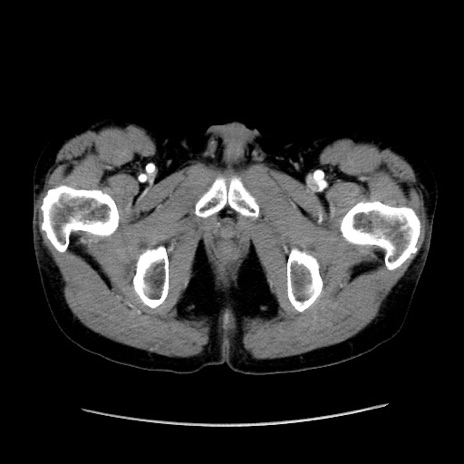

症例37(横断像)

【症例】40歳代 男性

【主訴】腹痛

【現病歴】4時間ほど前に電車に乗車中に臍部上より腹痛出現。徐々に増悪し起立困難となり、救急外来受診。生ものは数日食べていない。今朝お雑煮を食べた。

【身体所見】BT 36.8℃、BP 117/84mmHg、HR 91/min、SpO2 97%、苦悶様、腹部:臍上部広範囲圧痛あり、反跳痛±

【データ】WBC 8100、CRP 0.03